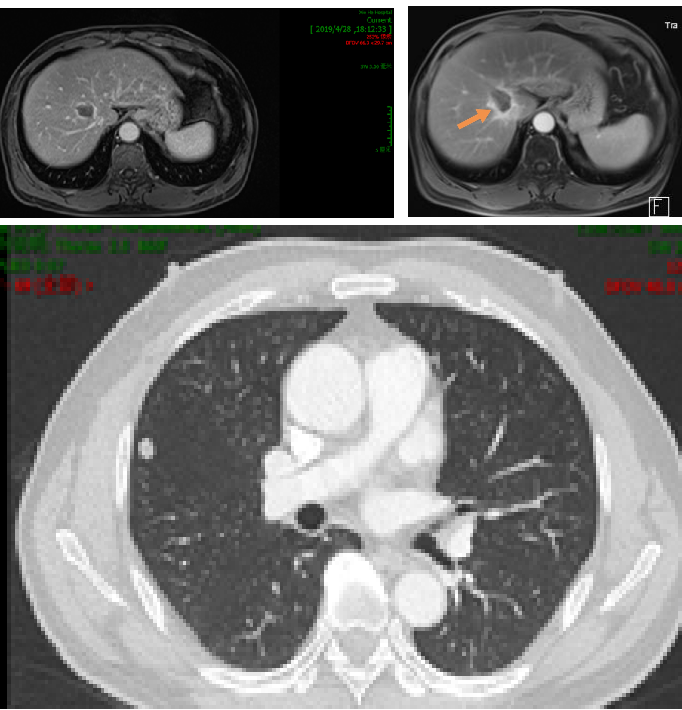

2019年3月胸部CT:右肺上叶近水平裂胸膜处有一枚结节,大小约6mm*5mm,考虑肿瘤转移;腹部MRI:肝右叶S8段新发结节,弥散受限,约16mm*12mm,考虑转移瘤可能性大。

2019.4.10于介入科行肝S8段转移瘤射频消融术。

因肝脏转移瘤靠近血管,射频消融术后复查CT认为肿瘤边缘存在强化,2019.5.27 行肝S8段转移瘤放疗,DT 40GY/5F。

2020.5.28 复查示肝脏及脑干病灶稳定,肺部结节略增大。

3. 肝右叶S8段异常强化灶,考虑转移性肿瘤,较前相仿;

4. 肝SVI段新发结节,考虑转移瘤;